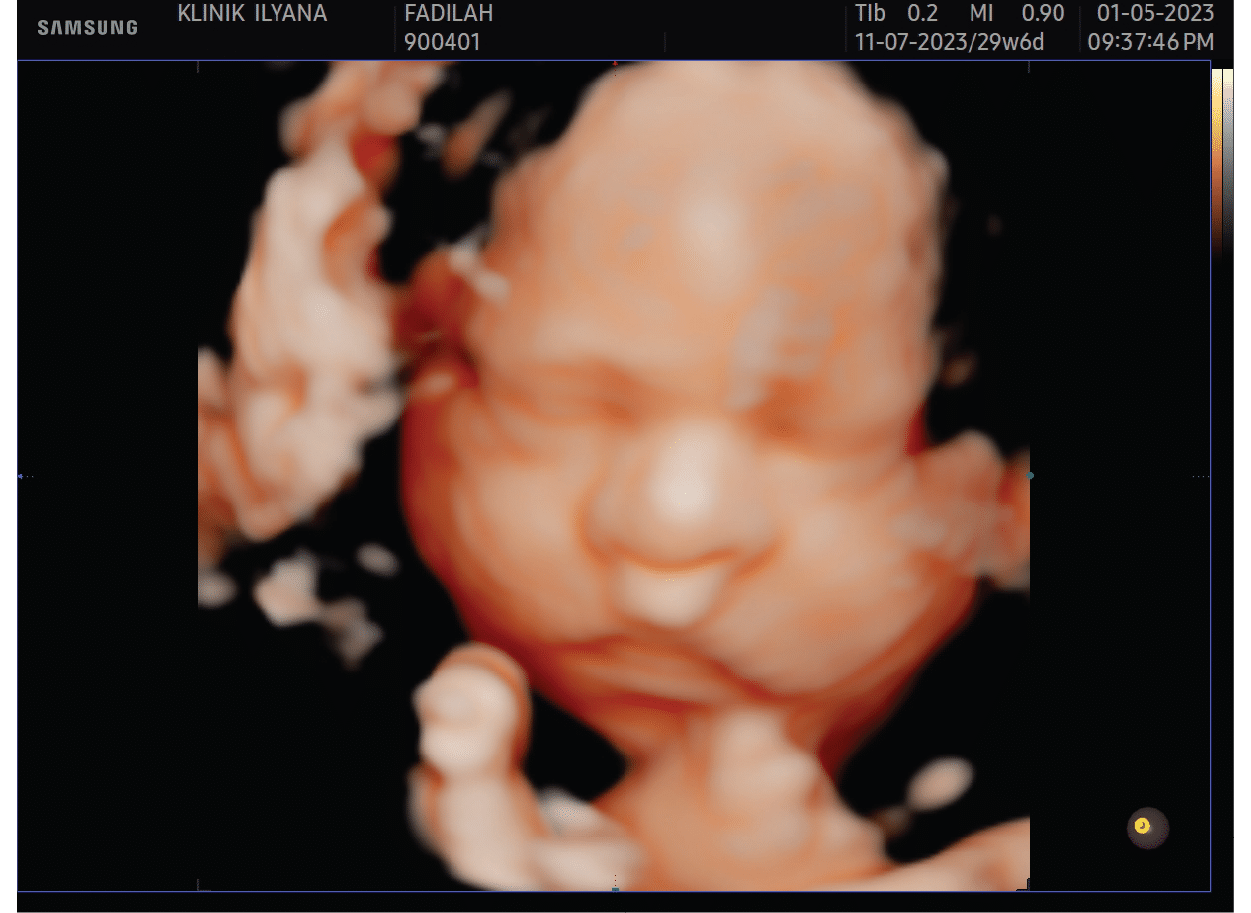

Includes pregnancy check-up / treatment (before / after) for pregnant mother